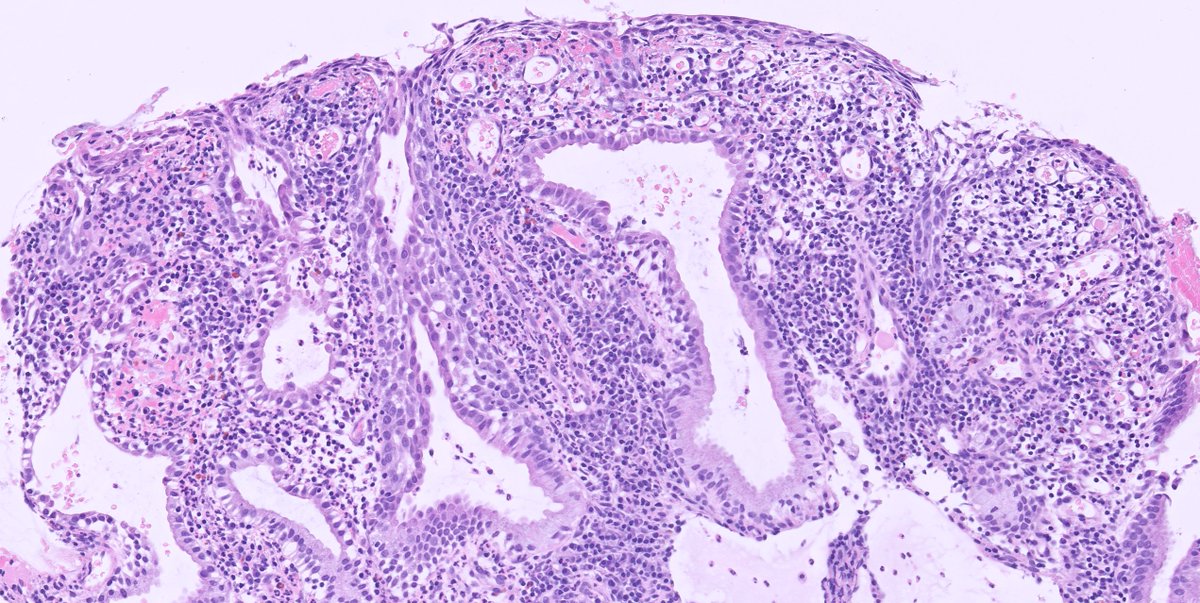

@skipocytes

Pathologist. Cases posted for interest and education with the pathology community, everything else sarcasm/humor. And the gifs. Oh, the gifs.